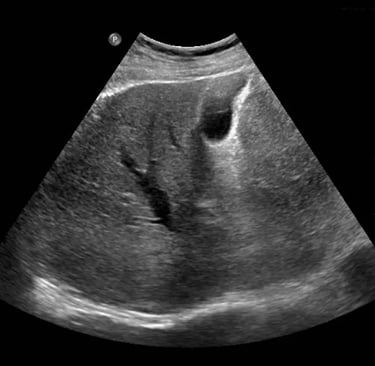

L’ecografia addominale rappresenta uno degli esami diagnostici per immagini più utilizzati e apprezzati in medicina, grazie alla sua non invasività, all’assenza di radiazioni ionizzanti e alla capacità di fornire informazioni in tempo reale sullo stato di salute degli organi interni.

L’ecografia addominale (spesso denominata “addome completo”) permette di visualizzare e valutare in dettaglio numerosi organi e strutture situate nella cavità addominale. Tra i principali elementi esaminati troviamo:

• Fegato: dimensioni, struttura, presenza di steatosi (fegato grasso), noduli, cisti o segni di infiammazione/cirrosi

• Cistifellea (colecisti) e vie biliari: ricerca di calcoli, infiammazioni (colecistiti), dilatazioni o ostruzioni

• Pancreas: valutazione di forma, dimensioni, presenza di masse, cisti o pancreatiti

• Milza: volume, omogeneità, eventuale ingrossamento

• Reni: forma, dimensioni, posizione, presenza di calcoli, cisti, idronefrosi o alterazioni parenchimali

• Vasi addominali maggiori (come l’aorta addominale): ricerca di aneurismi, trombosi o alterazioni di flusso

• Vescica (e vie urinarie): volume, pareti, residuo post-minzionale, calcoli o lesioni

• Organi pelvici (a seconda del sesso e del quesito clinico): utero e ovaie nella donna, prostata e vescichette seminali nell’uomo

L’esame consente inoltre di individuare masse anomale (cisti, tumori benigni o maligni), linfonodi ingrossati, liquido libero in addome o altre alterazioni che possono spiegare sintomi come dolore addominale, alterazioni degli esami del sangue, febbre di origine sconosciuta o controllo di patologie note.